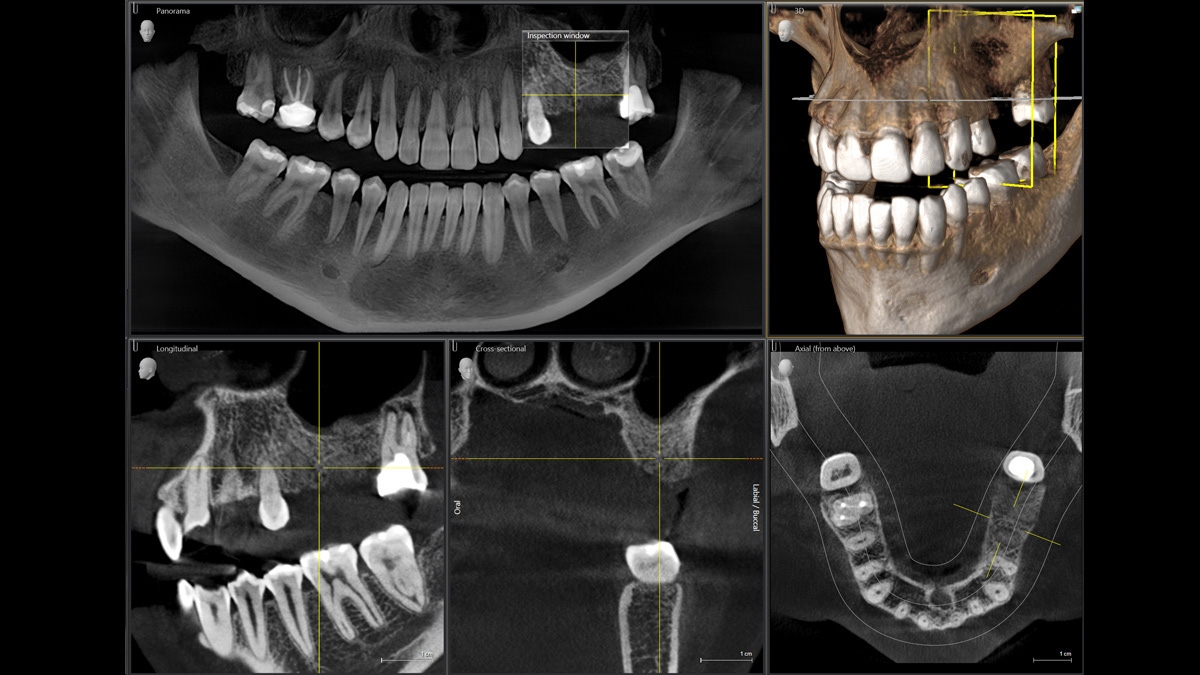

Za použití příslušného senzoru získáte laterální a symetrické předozadní ap/pa kefalo snímky i snímky zápěstí. V případech retinovaných zubů se můžete vrátit zpět k výhodám 3D rentgenů a stanovit jejich přesnou lokaci.